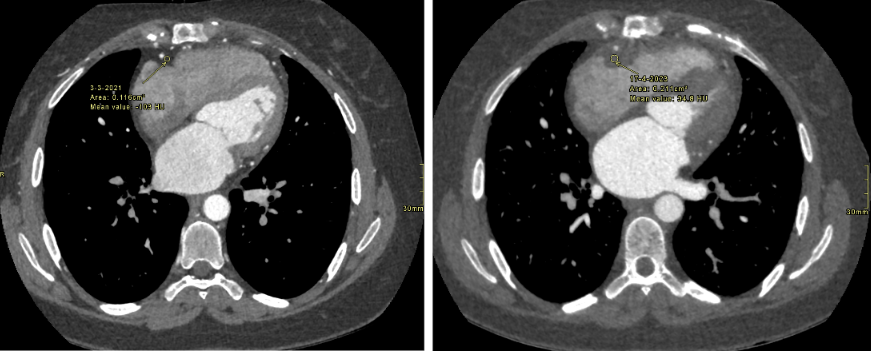

this picture shows the incresed RCA perivascular fat in a CCTA done 8 months before the acute MI compared with normal RCA perivascular fat in a CCTA done 2 years prior (both are done as a routine follow up and the patient had no symptoms at time)